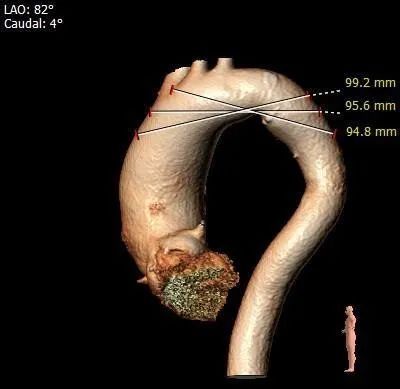

主动脉弓测量:

主动脉弓部宽度、角度可

•瓦氏窦、窦管交界内径可,升主动脉扩张